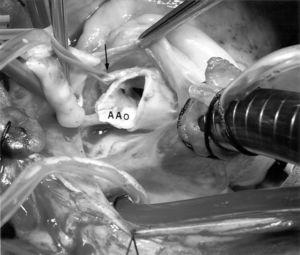

La paciente es intervenida quirúrgicamente (fig. 2), visualizándose el trayecto de la ACI entre la aorta y la arteria pulmonar. Se realiza transección del tronco de la ACI con un nuevo ostium en el seno coronario izquierdo y anastomosis del tronco de la ACI. Tras un postoperatorio sin complicaciones es dada de alta a su domicilio.

Figura 2. Observamos origen y trayecto inicial de la arteria coronaria izquierda (flecha negra). A Ao: arteria aorta.